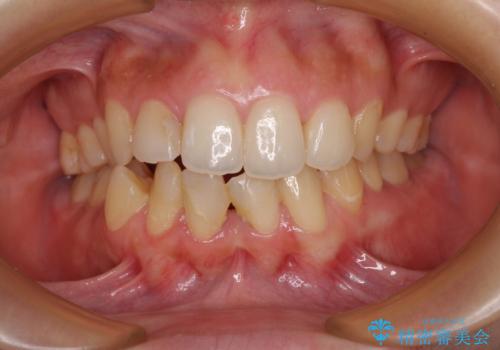

インビザライン・モデレートを用いて気になる後戻りを矯正治療

担当医 藤巻太一朗

前歯のガタつきを改善 抜歯矯正後の後戻り

担当医 草深敏毅